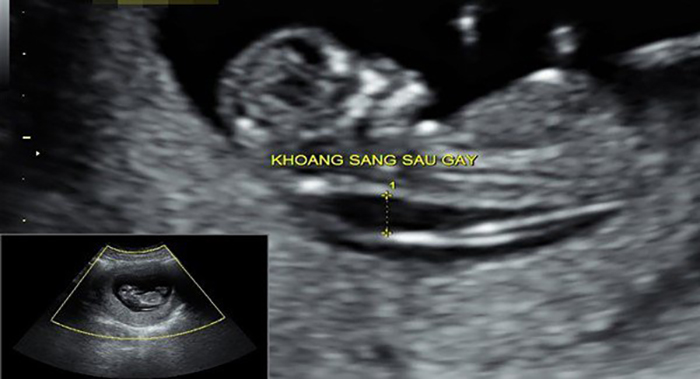

Ngoài việc giải đáp siêu âm 2D có đo được độ mờ da gáy thì ở phần này sẽ giúp các mẹ hiểu được cách đo độ mờ da gáy qua siêu âm 2D. Khi được chỉ định đo độ mờ da gáy qua siêu âm 2D, máy siêu âm sẽ quét toàn bộ bụng mẹ để lấy hình ảnh từ phần đỉnh đầu đến điểm cuối của xương sống. Dựa vào hình ảnh thu được, bác sĩ sẽ tiến hành đo độ mờ da gáy.

Hình ảnh siêu âm 2D đo độ mờ da gáy

Như trên hình ảnh, phần màu trắng chỉnh là làn da của bé, còn phần màu đen là các chất dịch tập kết ở sau gáy. Tại chỗ này, có một đường trắng xuất hiện và mờ dần chính là khoảng mờ sau gáy.